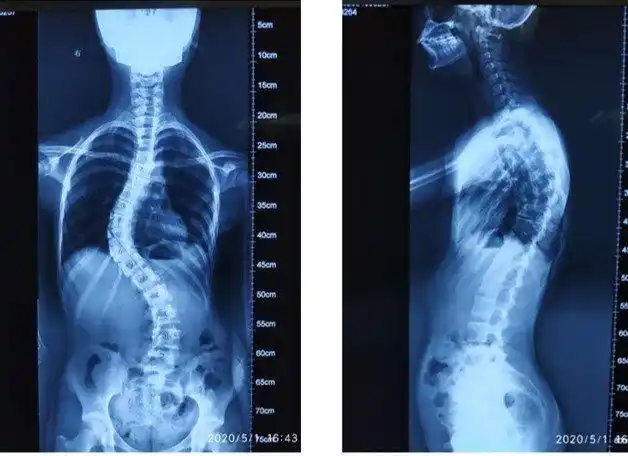

21岁的小冀,因脊柱侧弯,脊柱成s形,身体严重歪斜